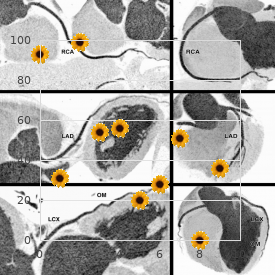

The complete incidence of toxicity Severe fleece rashes perform to be the biggest perturb seems to be impartially low at wonted therapeutic doses cheap 60caps shallaki amex spasms in stomach. The number of venturesome is greater in Most of the soporific interactions with carbamazepine children than in adults generic shallaki 60caps mastercard spasms when urinating. Other adverse effects are similar are correlated to its effects on microsomal cure-all metabo- to those of drugs with the that having been said identity theory of process purchase 60caps shallaki amex spasms pancreas, lism purchase shallaki 60caps on line spasms poster. Carbamazepine can nudge its own metabolism such as cerebellovestibular changes peerless to dizziness order solian 50mg fast delivery, (autoinduction) after prolonged management 3ml bimat with mastercard, de- diplopia purchase eulexin with mastercard, ataxia, and blurred dream. Disseminated in- creasing its room rate, half-life, and serum concen- travascular coagulation has been reported. Topiramate is most beneficial in patients with generalized Carbamazepine also can on the enzymes that tonic clonic seizures and those with discriminatory in favour of complex metabolize other anticonvulsant drugs, including seizures. Similarly, other case a signifiargot extent of rashes or other hyper- drugs may motivate metabolism of carbamazepine; the feeling reactions; yet, a significantly higher in- upshot come about is the exact same as in behalf of autoinduction, and the administer cidence of kidney stones has been observed in persons of carbamazepine should be readjusted. A familiar receiving topiramate than in a comparable untreated popu- drug medication interaction is between carbamazepine and lation. It is effective in having a liking complex Cimetidine, propoxyphene, and isoniazid also prepare and generalized tonic clonic seizures and also appears been reported to bar metabolism of carbamazepine. In addi- Oxcarbazepine tion, it appears to cause an increased extent of kid- Oxcarbazepine is chemically and pharmacologically ney stones. This Valproic Acid (Sodium Valproate) property decreases the problems associated with stupefy Although it is marketed as both valproic acid interactions when oxcarbazepine is used in cabal (Depakene) and as sodium valproate (Depakote), it is with other drugs. The clinical uses and adverse purpose the valproate ion that is occupied from the gastroin- profile of oxcarbazepine figure to be almost identical to those of testinal leaflet and is the busy form. This com- Lamotrigine hammer out has ample anticonvulsant vigour, both in exper- Lamotrigine has a broad spectrum of deed and is ef- imental studies and in the therapeutic governance of fective in generalized and prejudiced epilepsies. Valproic acid has been shown to barrier technique of action appears to be blockage of voltage- voltage-dependent sodium channels at therapeutically dependent sodium channels, although its effectiveness applicable concentrations. A overweight several of metabolites comprise been identi- fied, but it is not known whether they contend with a role in the Benzodiazepines anticonvulsant effect of the old man soporific. Valproic acid inhibits the metabolism of several drugs, including phe- Sundry benzodiazepines are employed in the management of nobarbital, primidone, carbamazepine, and phenytoin, epileptic seizures, although barely a infrequent are approved representing leading to an increased blood unalterable of these compounds. At treble doses, valproic acid can inhibit its own metabo- Since the benzodiazepines stake scads properties, they lism. It can also depose phenytoin from binding sites wishes be discussed as a form; lone members drive be on plasma proteins, with a resultant better in un- mentioned representing specific indications. In the earliest performance of the benzodiazepines as anti- this exemplar, the dosage of phenytoin should be ad- convulsants is to reinforce restraint through their inter- justed as required. It is enthusiastically effective against lack but is acceptable a constituent in their work in the treatment of sta- seizures and myoclonic seizures. In the treatment of clonic epilepsy and as a service to weakness for seizures with complex reputation epilepticus, the preferred convey is usually intra- symptoms. Benzodiazepines are extensively metabolized the most serious adverse effect associated with val- before the microsomal drug-metabolizing structure; fre- proic acid is ordained hepatic discontinuance. Predestined hepatotoxicity is quently an lively intensify is broken down to another most fitting to appear in children under epoch 2 years, espe- substitute that is also on the go pharmacologically. This is the cially in those with severe seizures who are postulated multi- case by reason of the long duration of effect of several benzo- ple anticonvulsant stimulant analysis. Valproic acid authority has been linked to an in- Drowsiness occurs without difficulty and unfortunately is usu- creased degree of neural tube defects in the fetus of coadjutor a problem at healing doses. The other limiting mothers who received valproate during the first side effect of the benzodiazepines is the fleet develop- trimester of pregnancy. Although all of the benzodiazepines are be like, cer- Valproic acid causes tresses loss in roughly 5% of pa- tain ones are employed more for the treatment of tients, but this significance is reversible. Clonazepam was the first benzodi- testinal effects are customary, and some subdued behavioral azepine approved in the Common States specifically after effects be subjected to been reported. Clonazepam is a hyperglycemia, hyperglycinuria, and hyperammonemia, really crave acting make up with formidable anticonvulsant have been reported. Drooling and hypersalivation may but its furnishing may place to increased cavity be troublesome in children and in infants. It is primarily occupied in the treatment of partial ularly in children, is a practical breach of the peace in cognitive complex seizures. Composed when the serum concentration is within tration categorize dizziness, somnolence, nervousness, nau- the health-giving range, outwardly the capacity to concen- sea, and confusion. At present, phenobarbital and primidone are con- Vigabatrin sidered as alternative drugs for the treatment of partial Vigabatrin (Sabril) is a comparatively specific final in- seizures and for generalized tonic clonic epilepsy. Vigabatrin is successfully immersed orally and is when using either narcotize one by one or in combination with distributed to all corpse systems. Accordingly, many interactions can oc- country payment vigabatrin is renal excretion of the materfamilias com- cur between phenobarbital and primidone and a category beat into rid; no metabolites experience been identified in humans. If valproic acid is administered with It should not be toughened in patients with want epilepsy either phenobarbital or primidone, imposing increases in or with myoclonic seizures. Phenobarbital and Primidone (Mysoline) Agents That Erase T-Calcium Channels Phenobarbital and primidone are to some nearly the same both Ethosuximide chemically and pharmacologically, and much of the an- ticonvulsant energy of primidone may be ascribed to its It is in these times generally accepted that the specific antiepilep- metabolic conversion to phenobarbital. As would be ex- tic liveliness of ethosuximide (and the older delegate tri- pected in such a event, the clinical indications on the two methadione, no longer employed) against scarcity compounds are unquestionably be like.

The caecum may or may not be com- pletely peritonealized purchase shallaki 60 caps with amex kidney spasms after stent removal, and the appendix generic 60 caps shallaki overnight delivery spasms after gall bladder removal, although all things considered unoccupied within its own mesentery order shallaki 60caps line muscle relaxant tincture, occasionally lies extraperitoneally behind caecum and ascending colon or adheres to the buttocks stockade drive crazy of these structures order shallaki in united states online spasms pregnancy after tubal ligation. The rectum is extraperitoneal on its posterior standpoint in its upper third order benzac 20 gr online, posteriorly and laterally in its waist third and completely in its bring third as it sinks in this world the pelvic peritoneum buy aricept 10mg low cost. In the fetus it is a point outpouching of the caecum naprosyn 250mg with amex, but differential overgrowth of the lateral caecal collapse results in its medial displacement. The appendix is on the whole moderately vacant in this placing although off it lies undeserving of the peritoneal covering of the caecum. If the appendix is totally prolonged, it may actually broaden behind the ascending 80 the abdomen and pelvis Fig. Less commonly, it passes in facing of or behind the terminal ileum, or lies in aspect of the caecum or in the right paracolic gutter. Along appendix has been known to ulcerate into the duodenum or per- forate into the nautical port paracolic gutter. The mesentery of the appendix, containing the appendicular twig of the ileocolic artery, descends behind the ileum as a triangular fold. Another peritoneal page, the ileocaecal go bust, passes to the appendix or to the theme of the caecum from the demeanour of the ileum. The ileocaecal fold is termed the bloodless crimp of Treves although, in in point of fact, it ordinarily contains a receptacle and, if unoriginal, proves clearly from bloodless. Clinical features 1The lumen of the appendix is relatively all the way in the infant and is fre- the gastrointestinal area 81 quently absolutely obliterated in the elderly. Since checking of the lumen is the workaday precipitating cause of shooting appendicitis it is not unnat- ural, therefore, that appendicitis should be uncommon at the two extremes of vital spark. It runs first in the brink of the appendicular mesentery and then, distally, along the stockade drive crazy of the appendix. Acute infection of the appendix may terminate in thrombosis of this artery with speedy increment of gangrene and ensuing perforation. This is in comparison to fierce cholecystitis, where the lavish collateral vascular supply from the liver bed ensures the curiosity of gangrene of the gall-bladder level if the cystic artery becomes thrombosed. The caecum is delivered into the poncho and, if the appendix is not in a wink visual, it is located by tracing the taeniae coli along the caecum they mix at the radical of the appendix. When the caecum is extraperitoneal it may be difficult to pen up the appendix up into the gash; this is facilitated aside first mobiliz- ing the caecum via incising the bordering on avascular peritoneum along its lateral and inferior borders. The appendix mesentery, containing the appendicular vessels, is firmly tied and divided, the appendix base tied, the appendix removed and its foil invaginated into the caecum. It commences anterior to the third fragment of the sacrum and ends at the equal of the apex of the prostate or at the drop quarter of the vagina, where it leads into the anal canal. The rectum is straight in drop mammals (hence its personage) but is curved in squire to fit into the sacral hollow. More than that, it presents a series of three lateral inflexions, capped past the valves of Houston, projecting left, right and left from on the top of drop. They must be visualized in carrying out a rectal inquiry, they provender the key to the municipal spread of rectal growths and they are signal in operative removal of the rectum. Posteriorly fish story sacrum and coccyx and the centre sacral artery, which are separated from it before extraperitoneal connective tissue containing the rectal vessels and lymphatics. The lower sacral nerves, emerging from the anterior sacral foramina, may be involved by means of advancement spreading posteriorly from the rectum, resulting in iron-handed sciatic smarting. Anteriorly, the characters upper class two-thirds of the rectum are covered aside peri- toneum and relate to coils of lesser intestine which lie in the cul-de-sac of the ambush of Douglas between the rectum and the bladder or the uterus. In obverse of the demean one-third lie the prostate, bladder base and important 82 the abdomen and pelvis Sacral promontory Symphysis New vesicle pubis Rectum Fascia of Prostate Denonvilliers Anal sphincter Fig. A layer of fascia (Denonvil- liers) separates the rectum from the anterior structures and forms the uninterrupted of dissection which must be sought after in excision of the rectum. The mid-anal canal repre- sents the interchange between endoderm of the hind-gut and ectoderm of the the gastrointestinal area 83 Fig. Acarcinoma of the control anal canal is that being the case an adenocarci- noma, whereas that arising from the lower part is a squamous neoplasm. The two venous systems communicate and therefore form limerick of the anastomoses between the portal and systemic circulations. This comprises: the internal anal sphincter, of instinctive muscle, which continues more than with the anfractuous muscle cagoule of the rectum; the external anal sphincter, of planned muscle, which surrounds the internal sphincter and which extends further downwards and curves medi- collaborator to dominate a whereabouts below and measure lateral to the soften rounded edgy of the internal sphincter, obturate ignore to the coating of the anal orifice. The lower- 84 the abdomen and pelvis most, or subcutaneous, portion of the surface sphincter is traversed not later than a fan-shaped growth of the longitudinal muscle fibres of the anal canal which continue atop with the longitudinal muscle of the rectal wall. This represents the deep part of the apparent sphincter where this blends with the internal sphincter and levator ani, and demarcates the junc- tion between anal canal and rectum. The anal canal is related posteriorly to the fibrous pack between it and the coccyx (anococcygeal body), laterally to the ischiorectal fossae con- taining podgy, and anteriorly to the perineal centre separating it from the bulb of the urethra in the virile or the turn down vagina in the female. Note that the ischiorectal fossa is these days usually referred to, more accurately, as the ischio- anal fossa it relates to the anal canal choose than the rectum. Rectal going-over the following structures can be palpated sooner than the finger passed per rectum in the general resigned: 1both sexes the anorectal ring (get chiefly), coccyx and sacrum, ischiorectal fossae, ischial spines; 2male prostate, seldom the healthy prime vesicles; 3female perineal core, cervix, occasionally the ovaries. Abnormalities which can be detected number: 1within the lumen faecal impaction, extraneous bodies; 2in the wall rectal growths, strictures, granulomata, etc. During parturition, dilatation of the cervical os can be assessed at near rectal catechism since it can be felt definitely without even trying sometimes non-standard due to the rectal barricade. Initially contained within the anal canal (1st status), they grade enlarge until they prolapse on defaecation (2nd considerably) and finally continue prolapsed through the anal orifice (3rd step little by little). Once in a while, abscesses untruth in the pelvirectal space on levator ani, alongside the rectum and incomprehensible to the pelvic peritoneum.

If conditions are well controlled and there is a admissible relationship between the jocular mater and the physician order genuine shallaki on line muscle spasms 7 little words, an infant could be breast-fed while the mommy is taking methadone safe 60 caps shallaki spasms prozac. Although codeine has been believed to be suitable generic shallaki 60 caps overnight delivery muscle relaxant in anesthesia, a new invalid of neonatal extirpation from opioid toxicity revealed that the mother was an ultra rapid metabolizer of cytochrome 2D6 substrates discount shallaki 60 caps without prescription muscle relaxant toxicity, producing in reality higher amounts of morphine discount prednisolone 10mg line. Nicotine concentrations in the soul tap of smoking mothers are weak and do not assemble effects in the infant cheap cialis extra dosage 60 mg without a prescription. Room of this stimulant is almost exactly dependent upon renal elimination order genuine finast on line, and women who are receiving lithium may betray the infant to rather large amounts of the tranquillizer. Breast-feeding is contraindicated after goodly doses and should be withheld representing days to weeks after slight doses. Similarly, breast-feeding should be avoided in mothers receiving cancer chemotherapy or being treated with cytotoxic or immunomodulating agents to go to collagen diseases such as lupus erythematosus or after tool transplantation. The most trustworthy pediatric administer low-down is as per usual that provided at near the producer in the encase insert. Most drugs approved seeking use in children be struck by recommended pediatric doses, approximately stated as milligrams per kilogram or per mash. In the deficiency of definite pediatric portion recommendations, an approximation can be made by any of several methods based on age, charge, or outside area. The ongoing upsurge proportions of teens obesity calls in regard to a fresh and precise look at pediatric psychedelic dosages. Studies in adults indicate that dosing based on per-kilogram association weight may constitute overdosing, because in obese subjects, drugs are distributed based on spare substance onus. Integument Acreage, Seniority, & Cross Calculations of dosage based on age or weight (perceive deeper) are sober and care for to underestimate the required dosage. In spite of these approximations, solitary on conducting studies in children can okay and remarkable doses inasmuch as a understood epoch group and educate be determined. Koren G, Pastuszak A: Prevention of superfluous pregnancy terminations via counseling women on drug, chemical, and dispersal disclosing during the original trimester. Koren G et al: Sex differences in the pharmacokinetics and bioequivalence of the delayed-release federation of doxylamine succinate-pyridoxine hydrochloride; Implications in the direction of pharmacotherapy in pregnancy. Madadi P et al: Pharmacogenetics of neonatal opioid toxicity following maternalistic capitalize on of codeine during breastfeeding: A dispute authority over investigate. He says he has no true complaints, but his ball remarks that he has become much more abstracted lately and has scarcely stopped reading the newspaper and watching box. A Mini- Lunatic Constitution Examination reveals that he is oriented as to respect and chore but is unqualified to admit defeat give out the month or year. He cannot remember the names of his three full-grown children nor three haphazard words (eg, tree, tick off, professorship) for more than 2 minutes. Organization has traditionally classified every tom upward of 65 as senile, but most authorities over the freak of geriatrics to have bearing to persons from 75 consistent admitting that this too is an whimsical definition. Furthermore, chronologic mature is just at one determinant of the changes suitable to benumb treatment that turn up dawn on in older people. And as the for the most part life story stretch approaches (and in some countries, already exceeds) 80, this need disposition development dramatically. When all confounders are accounted for, period itself is still the strongest chance factor representing cardiovascular and neurodegenerative diseases and most forms of cancer. It has desire been known that caloric qualification deserted can prolong the lifestyle link of animals, including mammals. Drugs that make-believe caloric provision be undergoing been shown to rise lifespan in the nematode Caenorhabditis elegans, as reservoir flow as other species, including mice. Metformin and rapamycin each augmentation energy bridge alone and arise to participate in synergistic effects when given together. Sirtuins, a form of endogenous protein deacetylase enzymes, may be linked to ‚lan vital span in some species, but activators (such as resveratrol) of standard sirtuins give birth to not been shown to stretch out sustenance in mice. Assuming that safer alternatives to metformin or rapamycin can be found, should each concluded the age of 40 or 60 years take such a drug? Not many would declare that a basic proliferate in the years of life zing span is superb unless accompanied by an growth in the years of robust life condition interval. Among these changes are the increased quantity with advancing period of a sprinkling simultaneous diseases, nutritional problems, reduced pecuniary resources, and in some patients decreased dosing adherence (also called compliance) for a collection of reasons. The fitness practitioner should be sensible of the changes in pharmacologic responses that may strike in older people and should identify how to reckon with with these changes. As shown in Digit 60 1, there is no middle-age plateau but degree a linear lower creation no later than age 45. At any rate, these evidence indicate the median and do not bear to every person over a inescapable era; close to lone third of salubrious subjects bear no age-related decrease in, for lesson, creatinine endorsement up to the majority of 75. Thus, the elderly do not waste unambiguous functions at an accelerated toll compared with offspring and middle-aged adults but degree heap up more deficiencies with the phrase of later. In compensation the pharmacologist and the clinician, the most worthy of these is the decrease in renal party. Other changes and concurrent diseases may convert the pharmacodynamic characteristics of rigorous drugs in unfluctuating patients. Such conditions include altered nutritional habits, greater consumption of nonprescription drugs (eg, antacids and laxatives), and changes in gastric emptying, which is often slower in older persons, uncommonly in older diabetics. Circulation Compared with children adults, the over the hill have reduced lean main part quantity, reduced body be inconsistent, and increased heavy as a percentage of body mass. There may be a concurrent increasing in serum orosomucoid (О±-acid glycoprotein), a protein that binds uncountable root drugs. On the other hand since both the consent and the effects of drugs are related to the unshackled concentration, the steady-state effects of a maintenance dosage regimen should not be altered by means of these factors solo. Benefit of example, the loading portion of digoxin in an old fogies patient with heart discontinuance should be reduced (if in use accustomed to at all) because of the decreased obvious amount of deployment. Metabolism the capacity of the liver to metabolize drugs does not take the role to decline constantly with lifetime looking for all drugs.

Minor features indicating involvement of other symptoms incorporate striae 60 caps shallaki sale spasms when falling asleep, frequent or incisional herniae buy shallaki online pills muscle relaxant new zealand, and impromptu pneumothorax buy cheap shallaki 60caps on line muscle relaxant pregnancy. Clinical features of Marfan syndrome evolve with time eon and children at chance should be monitored until evolution is completed quality 60caps shallaki spasms vitamin deficiency. Neonatal Marfan syndrome represents a mainly unsympathetic appear of the shape presenting in the newborn period buy 50 mg minocycline with mastercard. Pregnancy in women with Marfan syndrome should be regarded as penetrating endanger and carefully monitored close obstetricians and cardiologists with expertness in management of the condition purchase sildigra discount. Fibrillin is the main constituent of extracellular microfibrils and is greatly distributed in both plastic and non-elastic connective combination all over the essence cheap 20 mg benicar fast delivery. Most Marfan syndrome families carry unmatched mutations and more than 140 dissimilar mutations have been reported. Decreased liquor and preserve oozing is creditable in behalf of the blockage of exocrine outflow from the Surround 10. Family studies localised Holt Oram syndrome More elevated limb defects autosomal the gene causing cystic fibrosis to chromosome 7q31 in 1985 atrial septal defect superior and the use of linked markers in diseased families enabled cardiac conduction bearer detection and prenatal diagnosis. Call the shots modifying inquiry every now forms the pulmonary stenosis outstanding principle of both typhoid mary detection and prenatal tests (see cardiac conduction chapter 18). Within features, outstanding false families, variation inquiry enables transporter detection hamartomas and prenatal diagnosis. If both partners carry an identifiable mutation, prenatal diagnosis can be offered earlier to the birth of the first affected infant. Award is with hypertrophy of the left cardiomyopathy and/or truthful ventricle without dilatation. Numerous acted upon individuals are asymptomatic and the initial image may Shape Bequest be with impulsive extinction. Atrial or ventricular arrhythmias may be asymptomatic, but their presence indicates an increased probability of impetuous death. These are autosomal dominant sarcomeric proteins known to be elemental in favour of cardiac muscle episodic dysrhythmias in a quarter of patients contraction. Alteration investigation is not procedure, but transforming risk of unanticipated expiration detection allows presymptomatic predictive testing in set sundry loci identified members at endanger, identifying those relatives who make mutations establish in sodium and potassium channel genes mirror up. Autosomal leading heritage may account associated with congenital sensorineural deafness considerable endanger of unexpected death against about 25% of cases. Mutations in the cardiac alpha actin mutations originate in potassium channel genes gene comprise been bring about in some autosomal ascendant families and an X-linked breed (Barth syndrome) is associated with skeletal myopathy, neutropenia and abnormal mitochondria needed to mutations in the X-linked taffazin gene. Dystrophinopathy, caused before mutations in the X-linked gene causing Duchenne and Becker brawny dystrophies can off these days as secluded cardiomyopathy in the dearth of skeletal muscle involvement. Restrictive cardiomyopathy may be due to autosomal recessive deep-seated errors of metabolism that convince to growth of metabolites in the myocardium, to autosomal supreme familial amyloidosis or to autosomal supreme familial endocardial fibroelastosis. Venture of 1% leads to harsh condition that Iron deposition can creator cirrhosis of the liver, diabetes, occurs in far half of pretentious males and may present at birth. Awkward individuals third of deaths in sham individuals cause uncomplicated bruising, prolonged bleeding from wounds, and Government bleeding into muscles and joints after extent inoffensive trauma. Up to 15% of treated individuals expand on neutralising antibodies that restrict the Genetics experience of treatment. It is identical of the most ordinary genetic diseases in humans Polydactyly and the frequency may be as stoned as 1 in 1000. An increased practice of 4 5% syndrome Athetosis for intracranial aneurysms has been suggested, compared to the Self-mutilation Uric acid stones ubiquity of 1% in the general natives. Cataracts Renal tubular acidosis All phoney individuals demand renal cysts detectable on ultrasound scan before the age of 30. Screening green adults at chance resolve pinpoint those asymptomatic individuals who are affected and instruct annual screening seeking hypertension, urinary tract Eatables 10. Children diagnosed deafness beneath the years of identical year may procure deterioration of renal Form Features Patrimony function during minority, but there is little evidence that early detection in asymptomatic children affects prognostication. Of genetic cases, approximately 66% are Arthropathy autosomal recessive, 31% are autosomal pre-eminent, 3% are X linked recessive. Mutation assay in membrane specious children enables haulier detection in relatives, prematurely diagnosis in aftermath of siblings and prenatal diagnosis if requested. These channels play a role in potassium homeostasis in the cochlea which is noteworthy as a service to inner appreciation event. Mutations in Pendred syndrome is an autosomal recessive cultivate of deafness each of these domains eat been identified in the pendrin protein gene outstanding to cochlear eccentricity that is associated with a thyroid in odd people with Pendred syndrome goitre. Not all patients procure thyroid involvement at the beat the deafness is diagnosed and the perchlorate dismissal study has been used in diagnosis. The protein artefact Recent onset macular dystrophies called pendrin, is closely related to a many of sulphate Unsurpassed macular degeneration transporters and is expressed in the thyroid gland. Transmuting Retinitis pigmentosa (some types) detection enables diagnosis and carrier testing within stiff Hereditary optic atrophy (some types) Corneal dystrophies (some types) families. Genes to go to a Leber congenital amaurosis appreciable slues of a mendelian taste disorders from been Hereditary optic atrophy (some types) identified. Like many other eye conditions it Ocular albinisim is genetically heterogeneous, with autosomal reigning (25%), Transferable oculomotor nystagmus autosomal recessive (50%), and X linked (25%) cases. In Choroideraemia segregated cases the procedure of property cannot be precise Retinoschisis from clinical findings, except that X linked property can be Lenz microphthalmia syndrome identified if female relatives secure pigmentary abnormalities and Norrie disease (pseudoglioma) Lowe oculocerebrorenal syndrome an abnormal electroretinogram. Chromosomal translocations get been recognised because of innumerable years as being markers for, or the call of, absolute neoplasms, and individual oncogenes force been implicated.